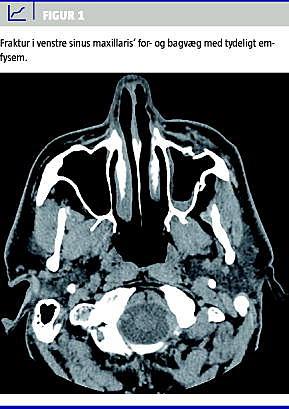

Ved ankomsten var patienten stabil, afebril og velbefindende fraset smerter i venstre del af ansigtet. Ved en objektiv undersøgelse fandtes den tidligere beskrevne flænge over kinden med synlig knogle i bunden samt subkutant emfysem over venstre kind. Der blev fundet normale forhold i ører, næse, mund og svælg. CT af ansigtsskelettet viste fraktur af sinus maxillaris' for- og bagvæg, små mængder blod i bihulen og moderat emfysem i parenkymet foran og bag ved venstre sinus maxillaris (Figur 1 ). Patienten blev sutureret i lokalanæstesi, og der blev påbegyndt peroral dicloxacillin- og benzylpenicillinbehandling. Han blev udskrevet i velbefindende dagen efter. Efter en ambulant kontrol og suturfjernelse en uge senere, hvor alle forhold var normaliseret, blev behandlingen afsluttet uden yderligere kontrol. Der var ingen kosmetisk betydende affladning af kinden, hvorfor man afholdt sig fra yderligere kirurgisk intervention.